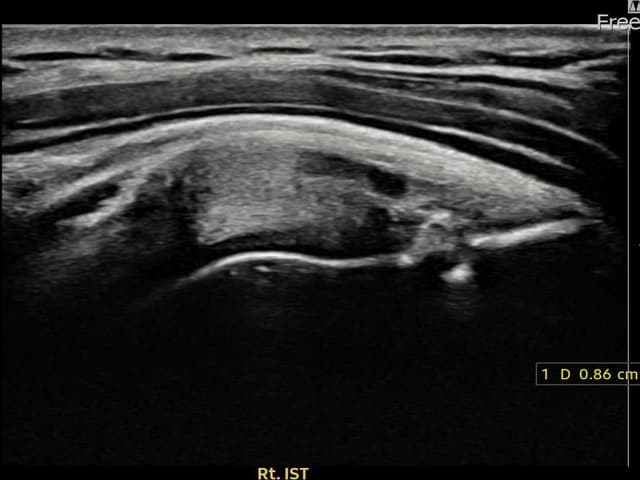

右侧 冈下肌腱 附着部部分撕裂

8.6mm × 4mm (肌腱厚度约45%缺损)